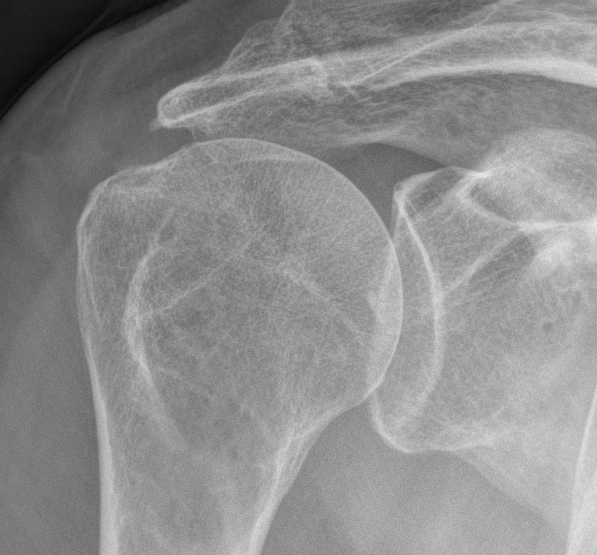

Xray

Look for: acromial morphology / high riding humeral head / rotator cuff arthropathy

Acromial spur / superior migration humeral head / rotator cuff arthropathy